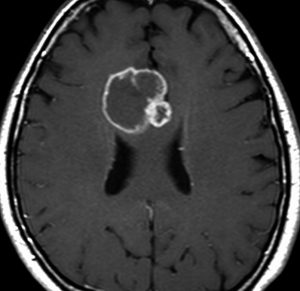

典型的な転移性脳腫瘍(単発)のMRI

腺癌の左前頭葉転移です。左のガドリニウム造影剤を使った画像では腫瘍が白く写っています。腫瘍の内部が一部壊死しているので黒っぽく見えます。右はフレア画像です。腫瘍の周囲の脳が腫れて脳浮腫(白く滲むようなところ)を生じています。

開頭手術で摘出した半年後の画像です。腫瘍は再発していなくて,脳の腫れも引いています。転移が発見された時には,見当識障害などの左前頭葉症状が強かったし,摘出がとても簡単な場所だったので手術しました。線状皮膚切開・小開頭ですから1時間くらいの簡単な手術です。でも,26mmくらいでしたから,定位放射線治療も可能なものでした。この患者さんは幸いなことに半年で再発していませんが,開頭手術による摘出だけだと同じ場所からまた再発することもあり,それから放射線治療を加えなくてはならないこともあります。個々の判断は難しいのですが,基本的には開頭手術より定位放射線治療のほうがいいと考えて下さい。